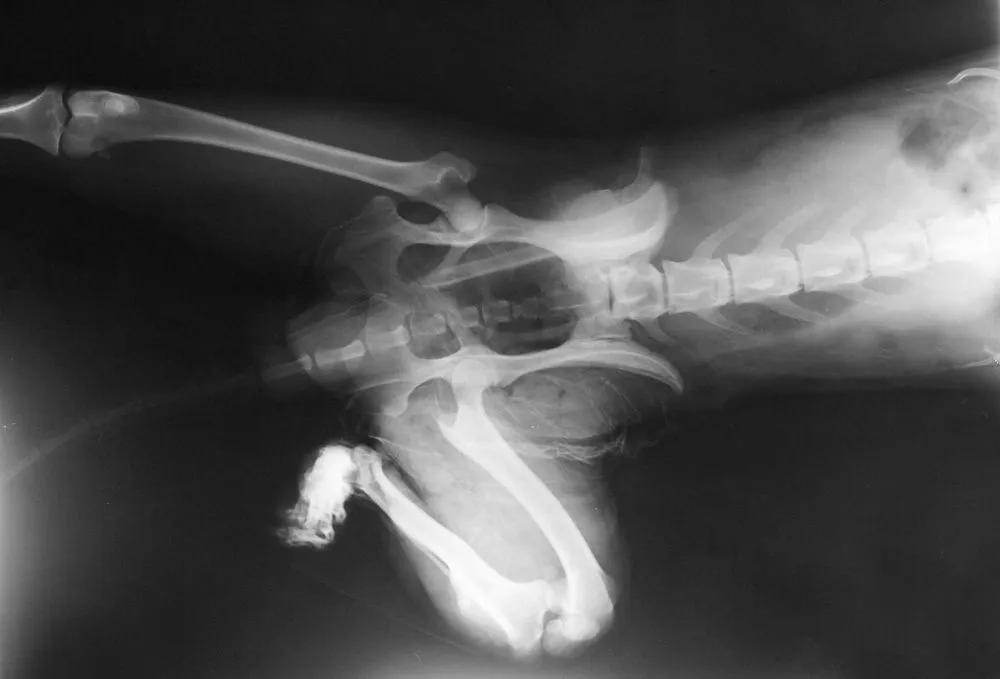

X-rays are a vital tool in veterinary medicine. They allow veterinarians to look beyond what is visible externally and examine your pet’s bones, joints, and internal organs. X-rays are particularly useful for diagnosing fractures, locating foreign objects, and evaluating issues such as respiratory distress or gastrointestinal blockages. When it comes to detecting and treating health problems, an x-ray for pet injuries can make all the difference in identifying the right course of action.

Pets may need an x-ray in various situations. Common reasons include sudden limping, visible swelling, or if your pet has experienced trauma. In other cases, x-rays may be used to investigate chronic conditions, such as arthritis or heart disease. If your pet is displaying unusual behavior or symptoms, a veterinarian near you, like the experts at Eola Point Animal Hospital, can determine whether an x-ray is necessary.